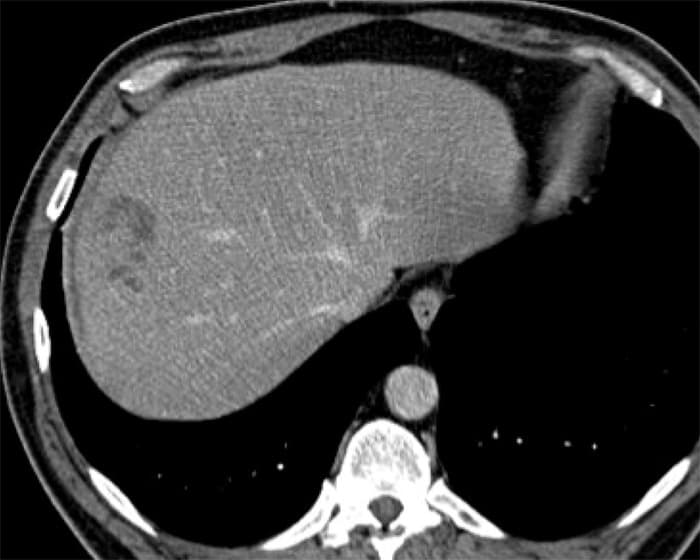

Sán lá gan

» Thông tin: Nam giới – 52 tuổi.

» Lâm sàng: Kiểm tra sức khỏe.